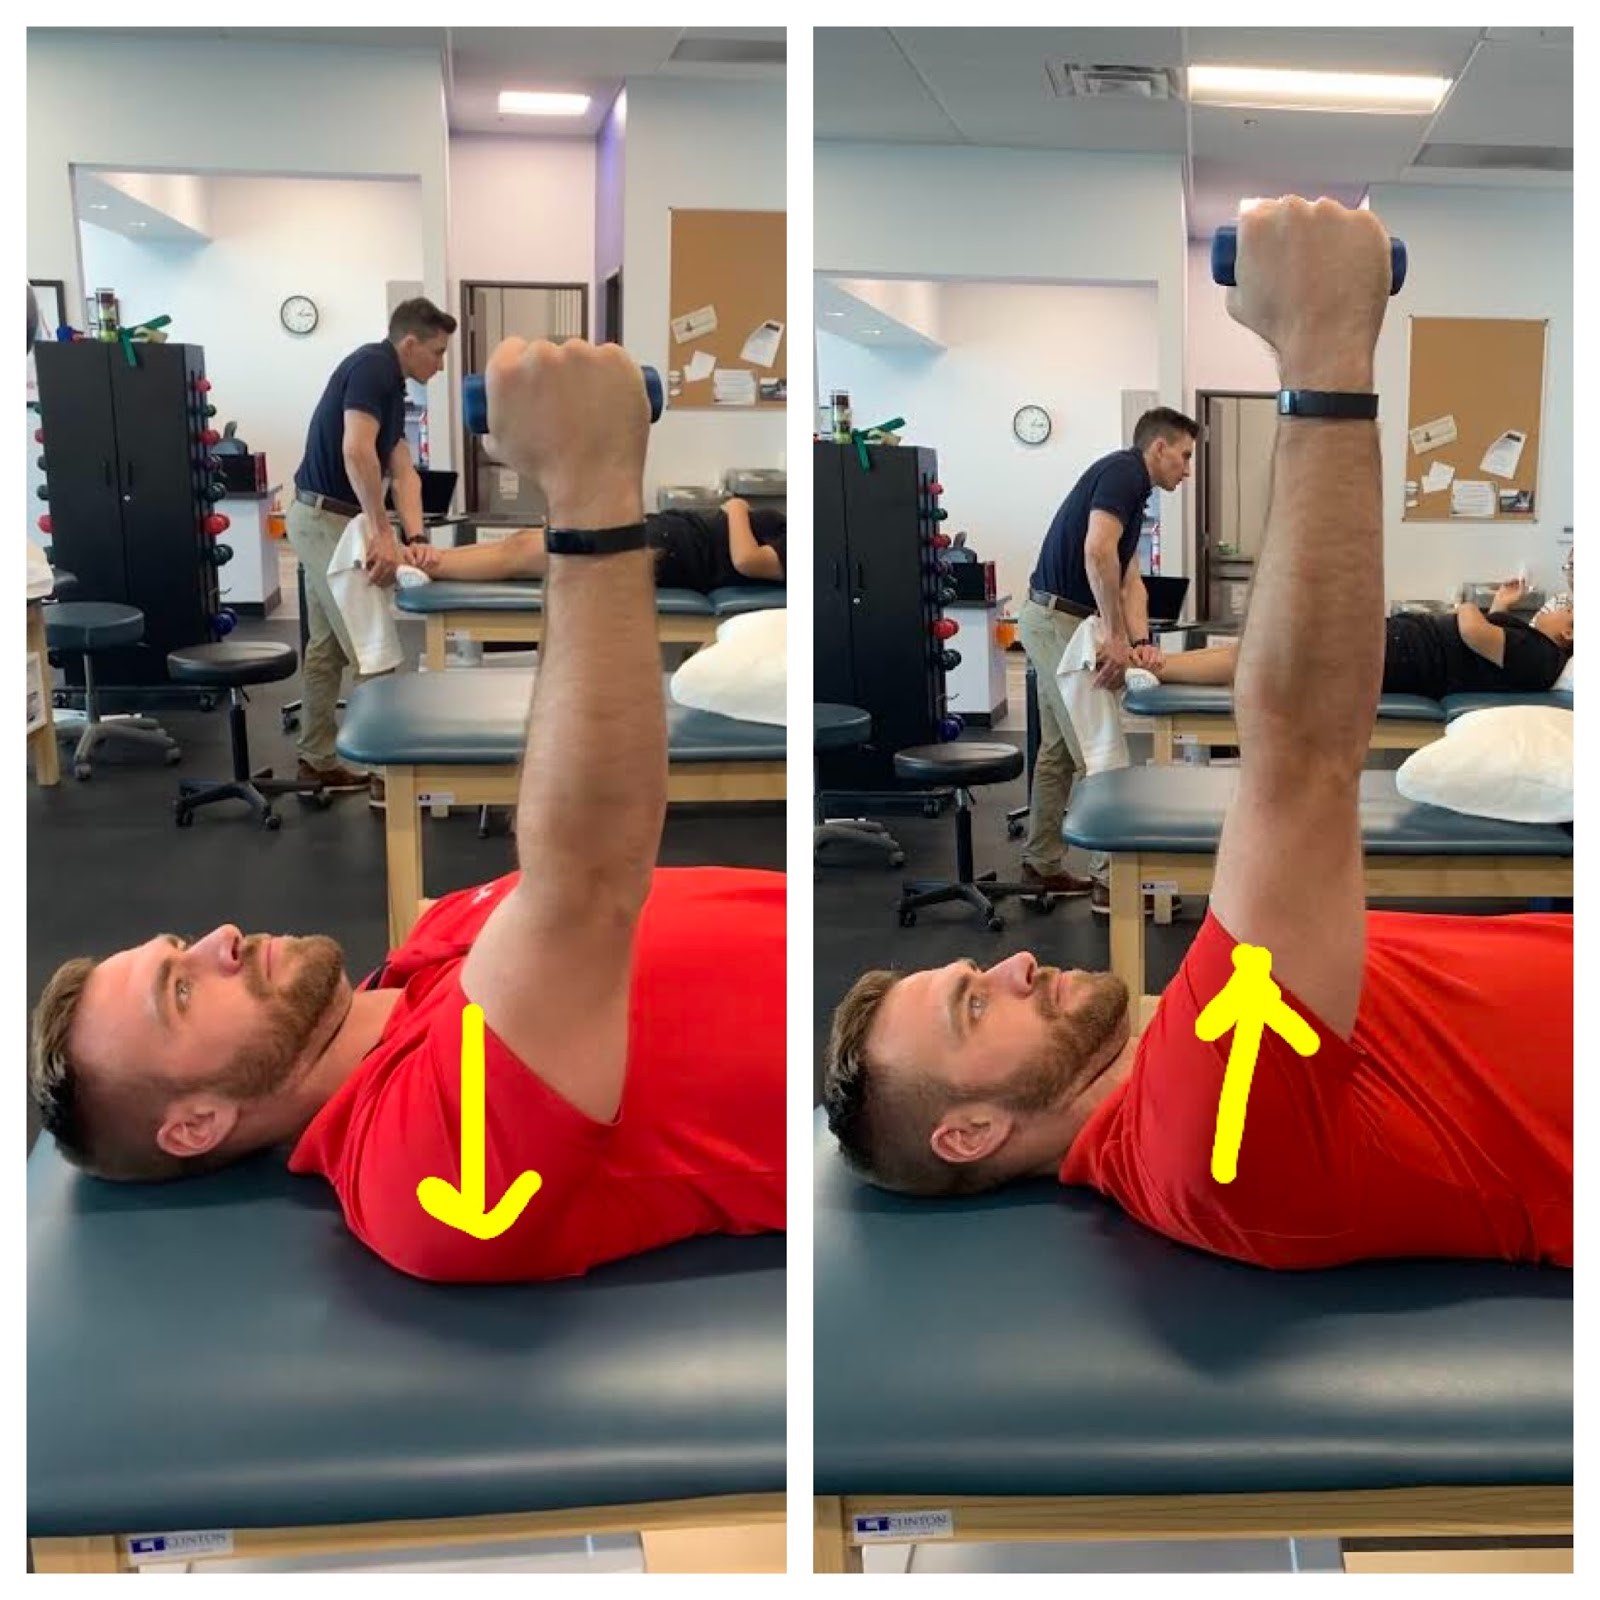

哪种治疗 DeQuervain 更好:夹板固定还是注射?

快速回顾 Cavaleri, R.、Schabrun, SM、Te, M. 和 Chipchase, LS (2016)。手部疗法与皮质类固醇注射在 de Quervain 病治疗中的比较:A ...

定制与预制拇指夹板治疗腕掌关节的比较:系统评价和荟萃分析

Baradaran, A.、Baradaran, A.、Ebrahimzadeh, MH、Kachooei, AR、Rivlin, M. 和 Beredjiklian, P. (2018)。定制与预制夹板治疗腕掌关节的比较:...